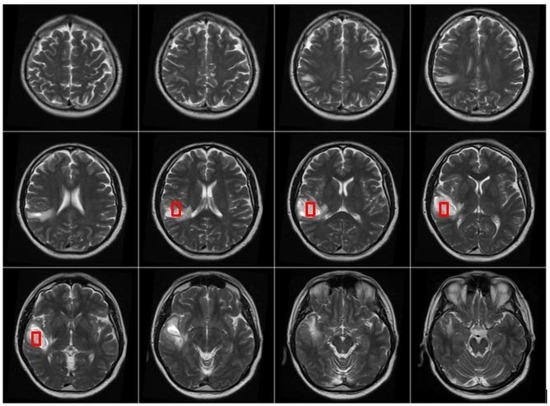

After the MRI brain scans are classified into normal and pathological images, the BBBGA method was applied on those identified as pathological cases as shown in the pathological patient in Figure 7. The red rectangles denoting the optimized 3D box refer to the pathological area in slices 6–9 where the tumor appears.

Figure 7. MRI brain scanning slices, the red rectangles denote the optimized location of 3D-box.